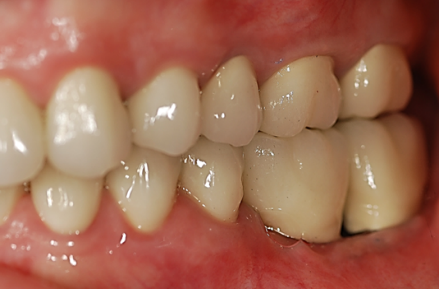

When there’s no available bone beneath the sinus floor (Fig. 1), we perform a full (external) sinus lift. We elevate the Schneiderian membrane and pack in bone graft material (Fig. 2). After 6-9 months, the new bone allows implant placement (Fig. 3). Four months later, those implants are restored with abutments and crowns (Fig. 4).

Fig. 4: Final Abutments and Crowns Seated on Implants